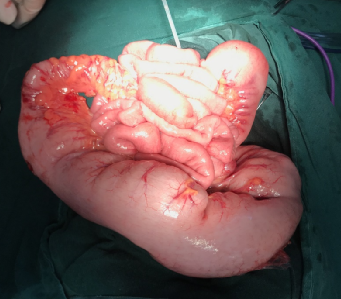

undefined

上图为先天性巨结肠术中所见扩张的结肠,似喇叭状,呈漏斗形